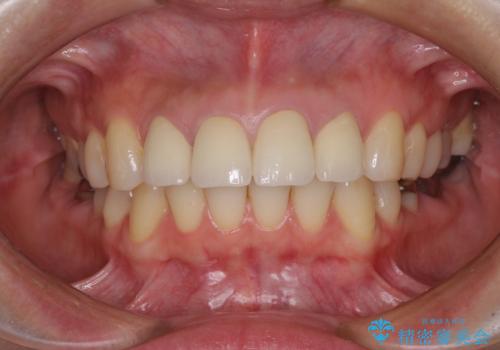

- 前歯のクラウンの変色や歯の変色を気にして来院された患者様です。

グラスファイバーを用いた土台により歯質を強化した上で、オールセラミッククラウンにて補綴することとしました。

統一感があり、歯肉ラインもきれいに整い、清潔感溢れる口元に仕上げることができました。